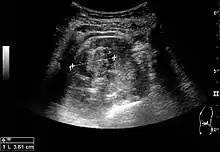

الموجات الفوق صوتية للكلى

في التصوير الفوق صوتي للكلى تظهر كتل كلوية صلبة بأصداء داخلية دون جدران واضحة في الكيس وتظهر في موجات دوبلر بانها أورام خبيثة أو لديها احتمالات عالية بأن تكون أورام خبيثة ويعتبر الورم الخلوي الكلوي الأكثر شيوعا بين الأورام الخبيثة حيث يمثل 86% من الأورام الخبيثة في الكلى حيث يتمركز السرطان الكلوي الخلوي على المتن ولكن يمكن أن يكون عالي الصدأ أو منخفض الصدأ ويوجد عادة على شكل مركز في اللب أو الجيوب الانفية ويمكن أن يكون التشقق في الغلاف متعدد البؤر وتحتوي على عناصر كيسية بسبب نخر التكلس حيث يرتبط سرطان الخلايا الكلوية بداء فون هيل والتصلب الجلدي ويوصى باستخدام الموجات الفوق صوتية كأداة لمتابعة الكتل الكلوية لدى المرضى.[2]